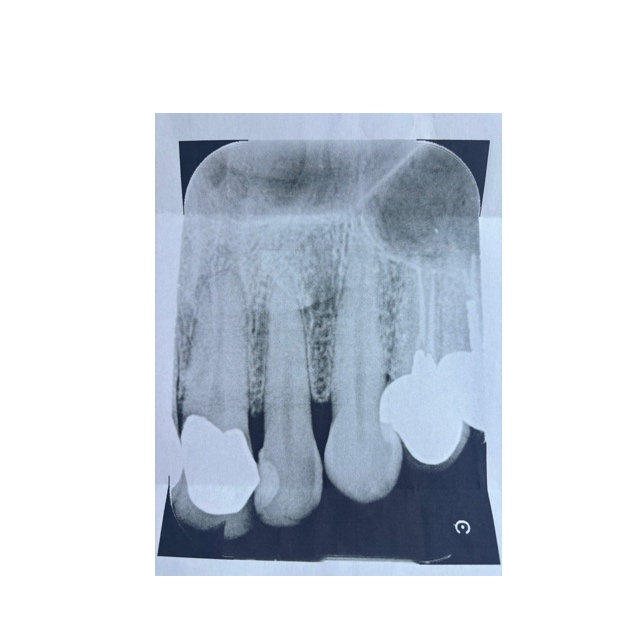

動揺1の左上2番の歯のレントゲン診ていただけますか?

歯周病、骨など問題はないと思います?先生から見て、この歯の寿命は長いと思いますか?

レントゲンから見て、左から2番目の歯です。